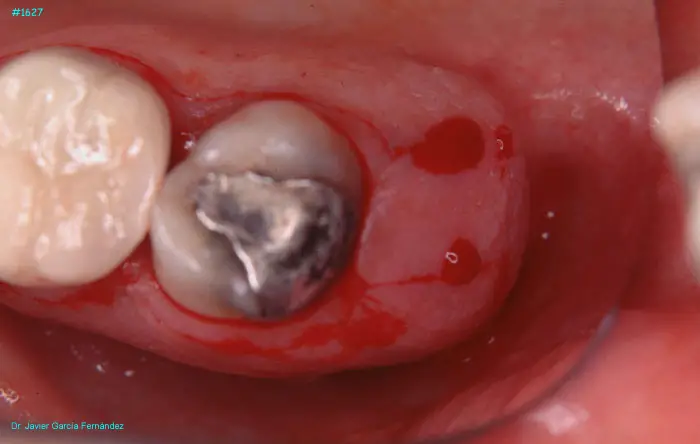

image 140